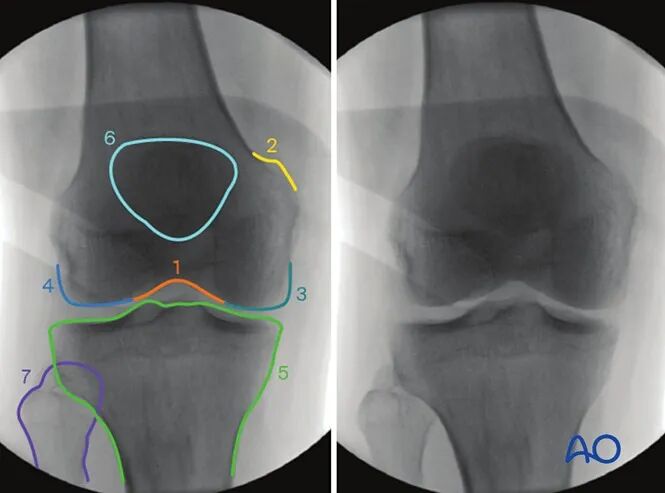

AO干货分享:

看胫骨平台是否平整的透视体位